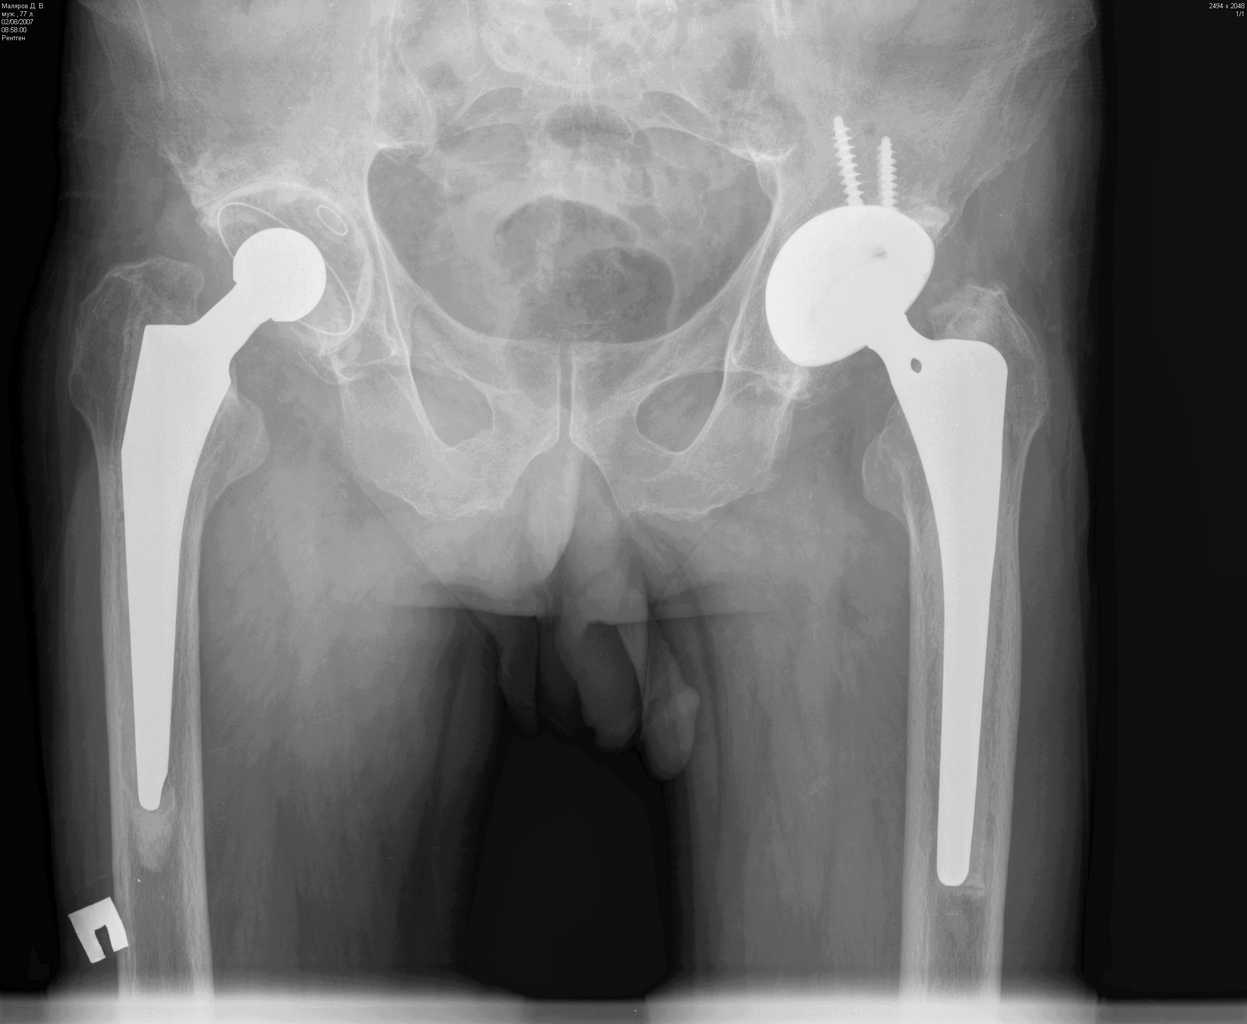

Уважаемые коллеги. Прошу оценить Р-граммы больного после протезирования т\б суставов.

Больной М.,75л. Страдает коксартрозом. В 2005 справа и в 2007 г. слева эндопротезирование т\б суставов.

Через полгода после операции появилась боль в правой паховой области, правом бедре(средней и верхней третях)при движениях и особенно осевой нагрузке на правую ногу.

На мой взгляд, оба бедренных компонента нестабильны, это и является причиной боли. Оба компонента явно меньше требуемого размера. Ножка Мюллера показывает отличные результаты, но только при формировании рассеченной цементной мантии.

Евгений, справа ножка нестабильна, возможно она уже развернулась в мантии, да и вокруг чашки есть просветления. Видимо надо планировать повторное вмешательство с удалением ножки и цемента. Ножка должна удалиться легко, цемент в значительной своей части тоже. Сменить ножку лучше на бесцементную и не обязательно ревизионную, пойдет любая с элементами диафизарной фиксации. Состояние впадины оцените во время операции.

Признаки нестабильности ножки заметные, выраженная демаркация зоны кость - цемент. Нестабильность чашки сомнительная. Согласен, не обязательно применение ревизионной ножки, но фиксацию предпочел бы цементную. Данный метод фиксации уменьшает риск интраоперационного перелома бедра, упрощает и ускоряет период реабилитации пациентов пожилого возраста. Вероятно, желательно применить другой тип ножки, я бы использовал CS (CSL) -PLUS Plus Orthopedics, т.с."бюджетный" вариант. Может возникнуть проблема с удалением цементной "пробки".

Уважаемый Евгений, понятие стресс шилдинга не является синонимом нестабильности, хотя и является признаком неадекватности распределения нагрузки в системе "имплантат - кость" и может в последствие привести к "расшатыванию" эндопротеза.В данном случае на рентгенограмме правого тазобедренного сустава отчетливо видна сформированная "замыкательная пластинка" на внутреней поверхности кости (на границе с цементом). Причем, как раз в проксимальном отделе сегмента, то есть в зоне определяющей стабильность имплантатов типа Мюллер.

Болевой синдром в тазобедренном суставе при осевой нагрузке не характерен для корешкового с-ма или ишалгии. В данном случае, скорее всего мы наблюдаем "обратный" "с-м поршня". Когда изменение давления в костномозговом канале за счет перемещения нестабильной ножки (поршня)передается не в дистальные отделы бедра (классический "с-м поршня"), а за счет неподвижной (или малоподвижной) цементной пробки "отражается" в проксимальную часть, где и возникает боль. Возможно, конечно и наложение неврологическои и ортопедической симптоматики. Но, на мой взгляд, данные рентгенограммы дают достаточно информации о наличие проблем, по крайней мере, со стороны ножки эндопротеза правого тазобедренного сустава. А R-граммы, действительно хорошие... по качеству.

На мой взгляд имеет место нестабильность обоих бедренных компонентов. Боль, которая имеет место у больного характерна при проблемах в области тазобедренного сустава. Нужно рассматривать вопрос о ревизионном эндопротезировании, в частности бедренного компонента.